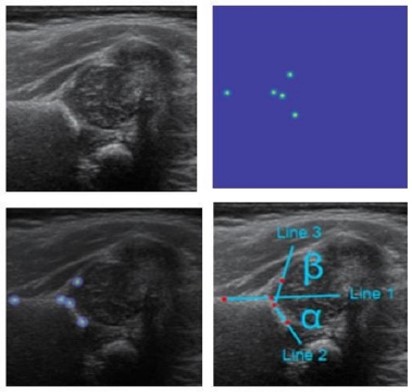

基於人工智慧之頭型歪斜程度評估方法

周邦昀

長庚醫院 顱顏中心學術組副教授

林口長庚紀念醫院

高軒楷

林口長庚紀念醫院 副教授

兒童骨科

技術亮點:

超音波偵測嬰兒髖關節角度

顱顏中心

歪頭症寶寶頭型歪斜程度評估